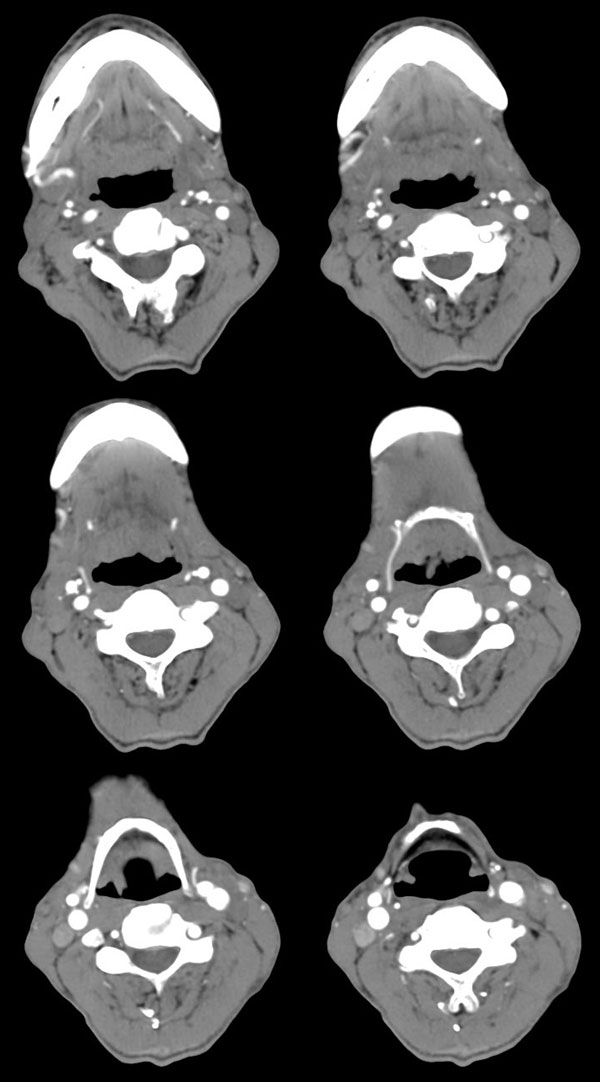

| 男性,57岁。反复声嘶1年,加重半年。 体检:喉粘膜充血,会厌肿胀,上举差,喉室及双声带窥视欠清。              蚂蚁发言:考虑喉癌(声门型)?双侧颈鞘周围淋巴结转移? 徐飞发言:有无呛水?根据病史要考虑球麻痹,脑干应检查 弯三角发言:考虑喉结核,应检查其它部位有无结核 卜一发言:喉腔右侧壁弥漫性软组织增厚,喉腔变窄。支持:喉癌(声门型)!另:双侧颈部多枚淋巴结肿大! 结果: 支纤镜检查:会厌板肿胀,右会厌咽侧壁肿胀,右杓状小结见结节样肿物,喉室肿胀,双声带肿胀、充血,左声带见菜花样肿物,触及易出血,取活检。 病理诊断:高分化鳞状细胞癌。 免疫组化:ck(h)(+++)、pcna(++)、p53(++)、ck(l)(-)。 原贴地址:http://www.radinet.com.cn/forum_view.asp?forum_id=4&view_id=34703 |